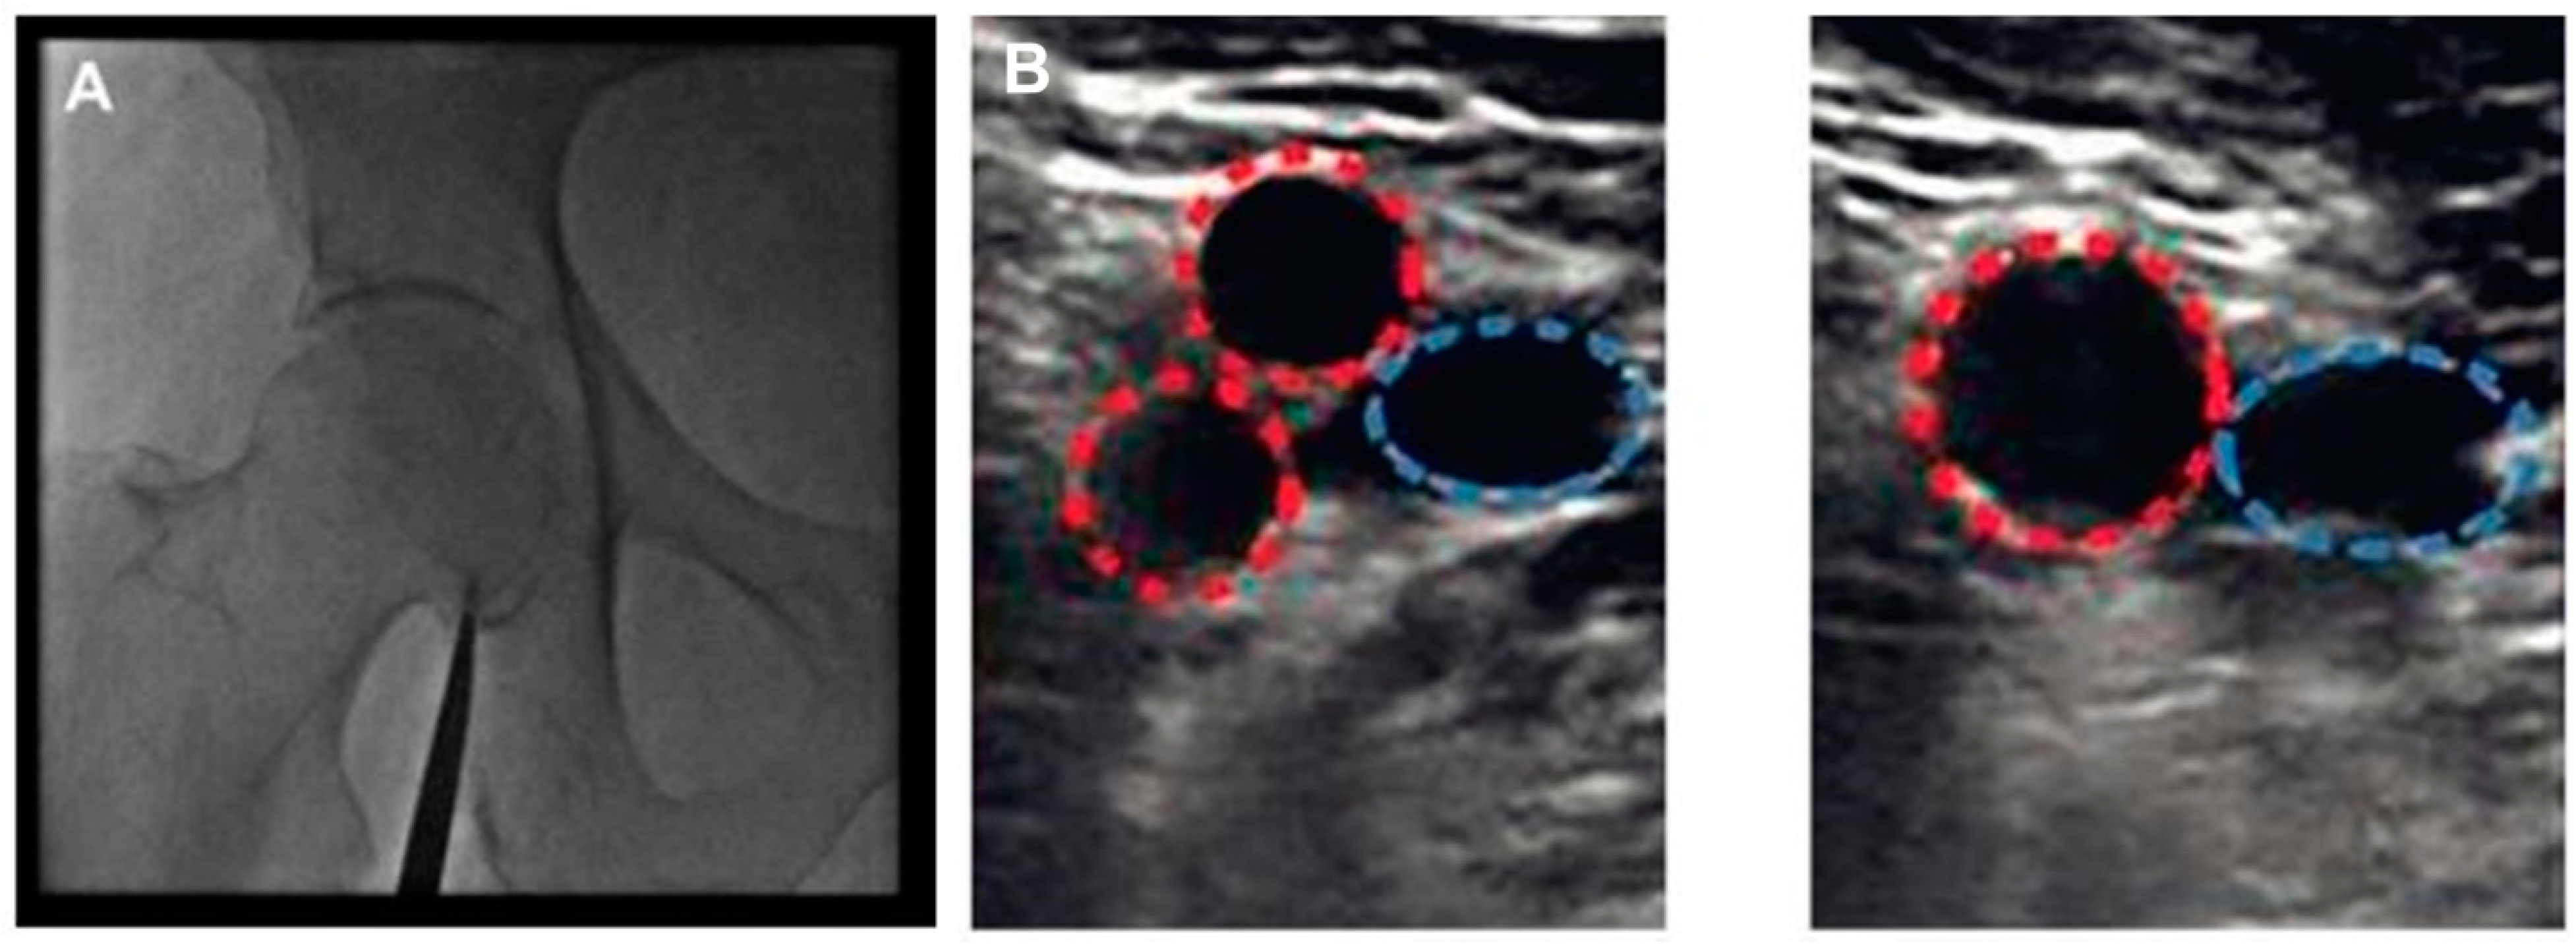

2. Existing Evidence Supporting the Use of Ultrasound-Guided Femoral Access